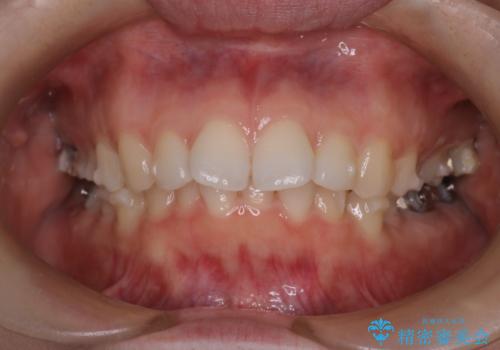

【インビザライン】前歯を引っ込めたい

- 前歯が出ていることを主訴に来院された患者様です。

抜歯を希望されなかっため、臼歯部の遠心移動やIPRを行い配列を行っています。

抜歯をしていない矯正となるため、口元に大きな変化は認められません。